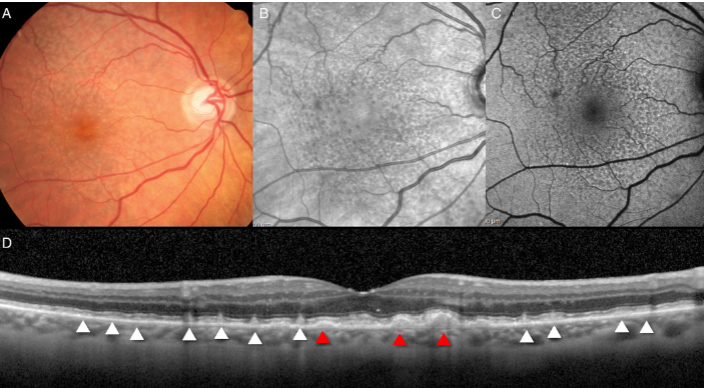

reticular pseudodrusen

subretinal drusenoid deposits

best imaged w/ AF, infrared reflectance, OCT

appear to be a meaningful risk factor to GA

reticular pseudodrusen

GA

GA

GA

GA

GA